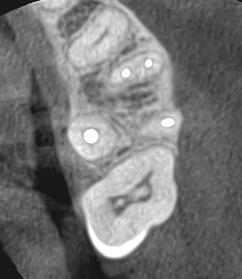

3D CBCT scanning for improved diagnosis